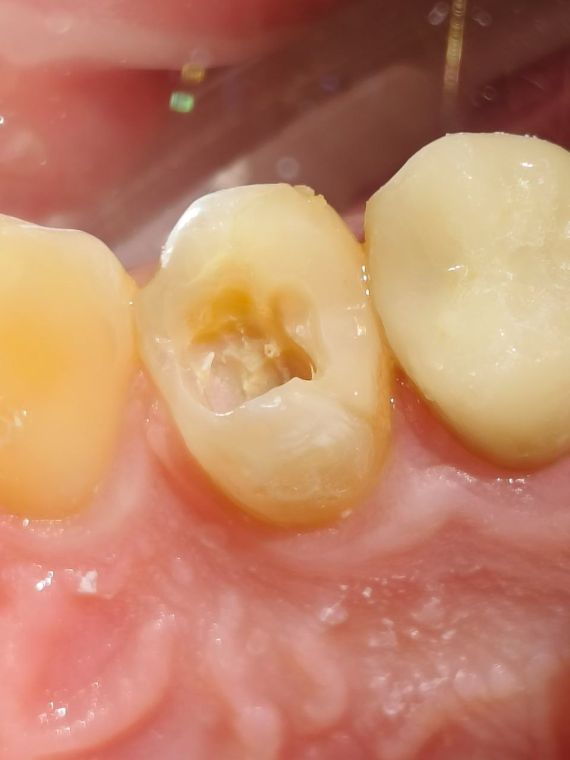

кариозный зуб

На фото представлен скрытый кариес на апроксимальной поверхности зуба

зуб до лечения

Кариес не всегда проявляется как темное пятно, такое бывает в случае поражения зуба с контактной поверхности. Эмаль остается целой, и просто слегка меняет цвет на "белесоватый. Такую полость легче всего увидеть на КЛКТ и рентгене.

Во время лечения

Как видно после "встрытия" зуба, ткани внутри более темного цвета и изменены по структуре. Дентин мягкий легко убирается инструментом